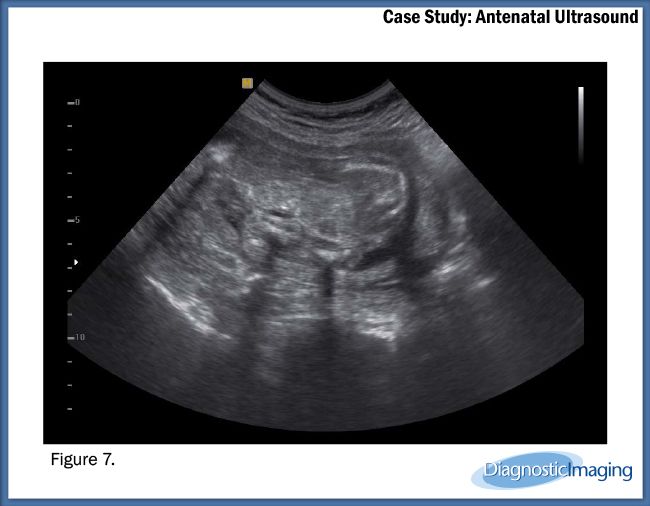

Case History: 25-year-old patient presents for antenatal ultrasound.